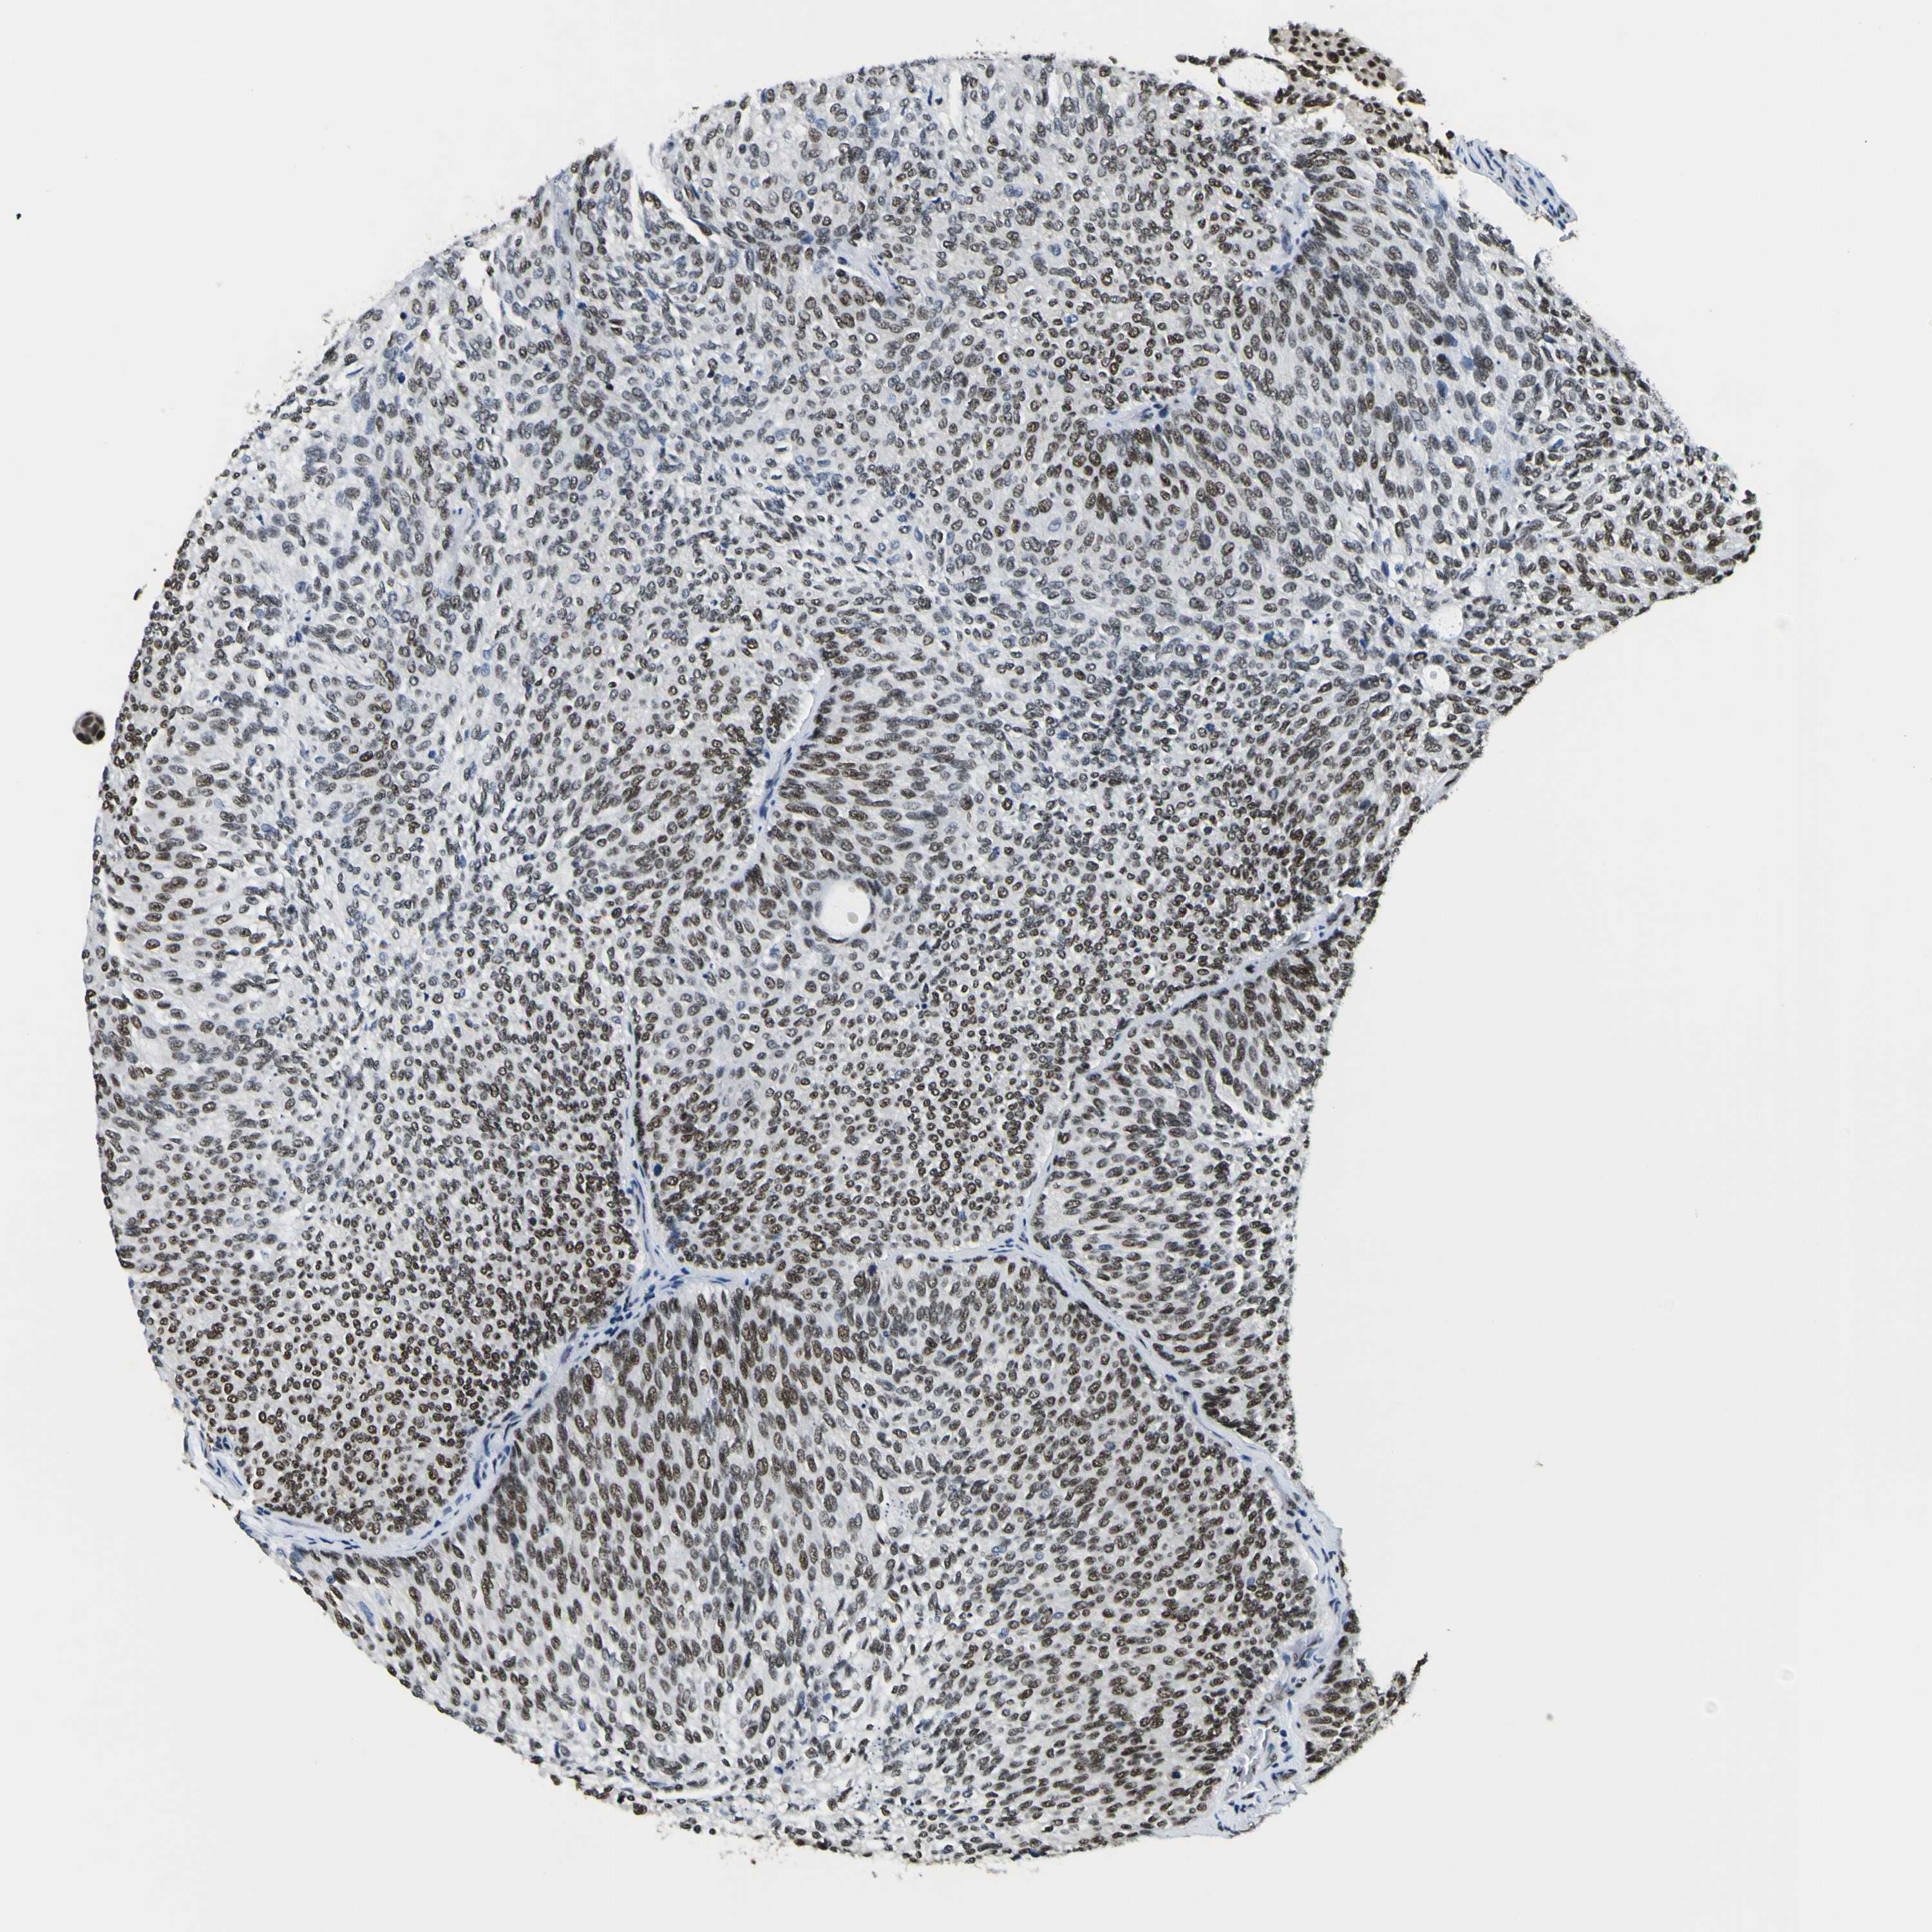

UROTHELIAL CANCER - Protein expressioni

A mouse-over function shows sample information and annotation data. Click on an image to view it in a full screen mode. Samples can be filtered based on level of antibody staining by selecting one or several of the following categories: high, medium, low and not detected. The assay and annotation is described here.

Antibody stainingi

Antibody staining in the annotated cell types in the current human tissue is reported as not detected, low, medium, or high, based on conventional immunohistochemistry profiling in selected tissues. This score is based on the combination of the staining intensity and fraction of stained cells.

Each image is clickable and will lead to virtual microscopy that enables deeper exploration of all samples and also displays staining intensity scores, fraction scores and subcellular localization as well as patient and tissue information for each sample.

Antibody HPA001853

Antibody HPA012292

Antibody CAB000330

Staining

High

Medium

Low

Not detected

Intensity

Strong

Moderate

Weak

Negative

Quantity

>75%

75%-25%

<25%

None

Location

Nuclear

Cytoplasmic/membranous

Cytoplasmic/membranous,nuclear

Urothelial carcinoma, High grade

Urothelial carcinoma, Low grade